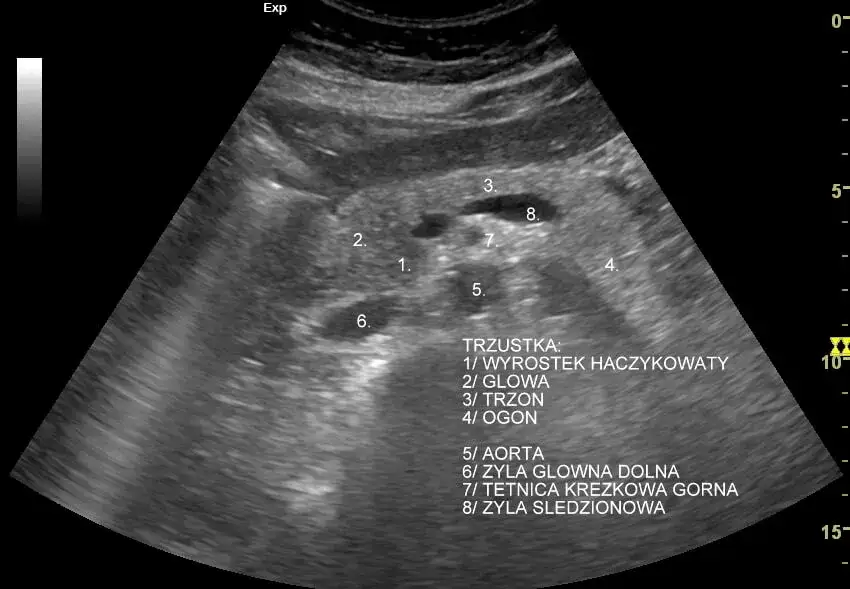

- USG jamy brzusznej: Pierwsze badanie obrazowe, pozwalające na wstępną ocenę wielkości, kształtu i struktury trzustki.

Kiedy potrzebujemy zajrzeć do wnętrza trzustki, najczęściej zaczynamy od ultrasonografii (USG) jamy brzusznej. To badanie jest szybkie, nieinwazyjne i łatwo dostępne. Pozwala mi ocenić wielkość, kształt i strukturę trzustki, a także wykryć ewentualne zmiany ogniskowe, torbiele czy poszerzenie przewodu trzustkowego. Należy jednak pamiętać, że USG ma swoje ograniczenia gazy jelitowe mogą utrudniać dokładne obrazowanie trzustki, która leży głęboko w jamie brzusznej.